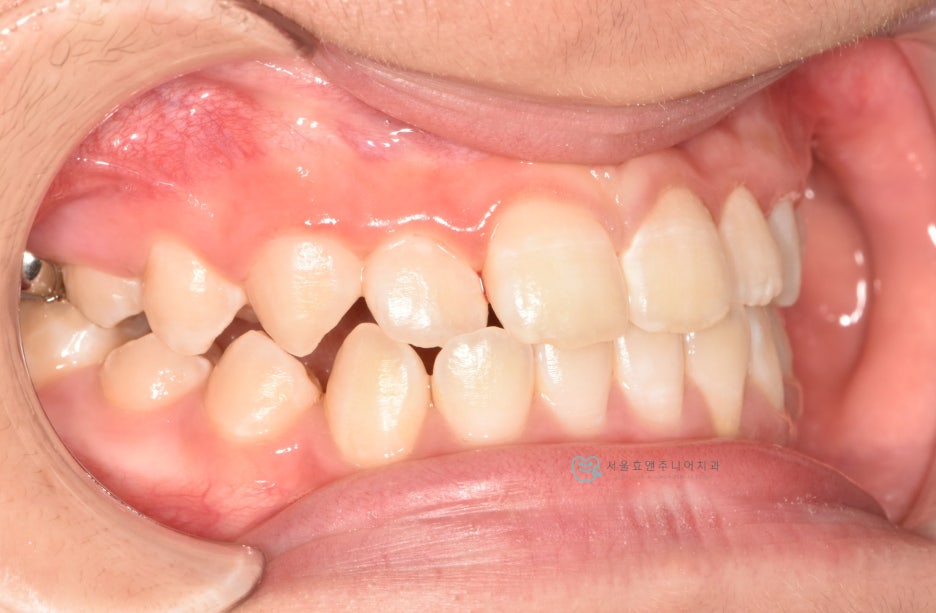

프리올소 착용 9개월 뒤

프리올소 착용 후 9개월 뒤 모습입니다. 앞니 반대교합이 수정되었습니다. 처음에 문제가 되고 있었던 아래앞니의 치은퇴축도 많이 개선되었습니다. 교합이 개선되어 치아의 위치가 바로잡히고, 치아에 무리한 힘을 더 이상 주지 않으니, 치은퇴축은 시간이 더 지나면서 점점 더 개선될 것으로 생각됩니다.